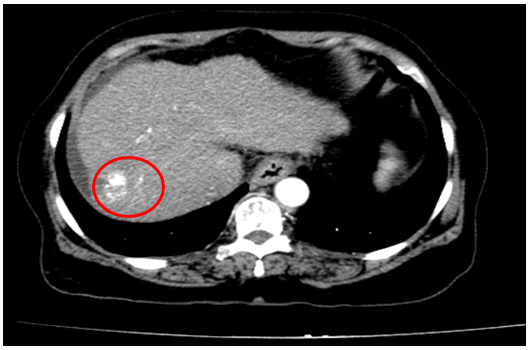

Chụp cắt lớp vi tính ổ bụng

Gan: biến đổi hình thái, bờ không đều. Nhu mô gan phải có khối giảm tỉ trọng kích thước 26x25mm, ranh giới không rõ, co kéo bao gan lân cận,trong có hình ảnh tăng tỉ trọng của vật liệu nút mạch, sau tiêm có phần ngấm thuốc ngấm thuốc.

Dịch quanh gan 8mm., dịch tự do ổ bụng

=> Hình ảnh u gan phải sau điều trị hiện còn phần ngấm thuốc (Vòng tròn đỏ) /Xơ gan